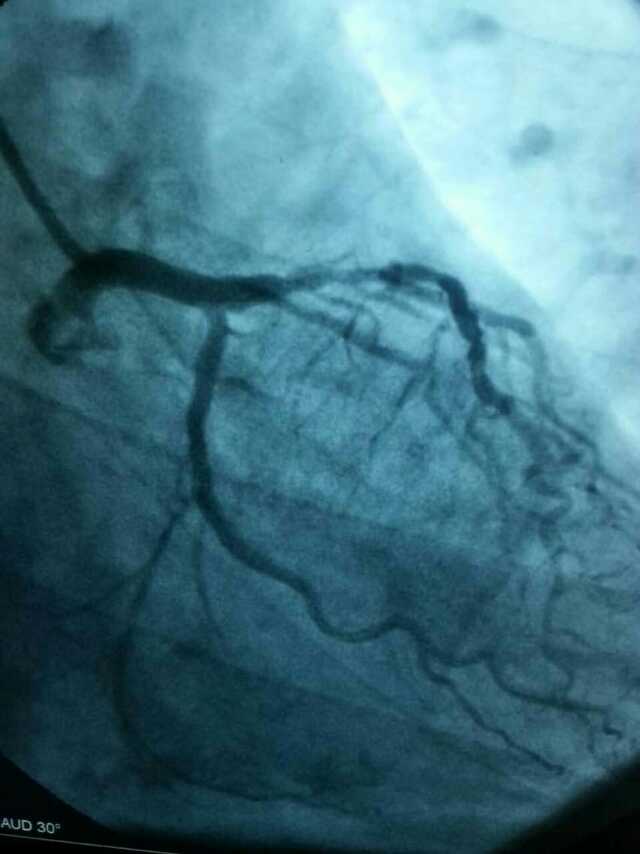

3月20日,家住翔安的庄先生为感谢91club 心血管内科的医护人员在第一时间对他的病情给予明确诊断,并及时采取有效治疗措施,让他的心脏病很快得到康复回家。特地送来一面写着“德医双馨,妙手回春”锦旗以表达他们满满的感激之情。